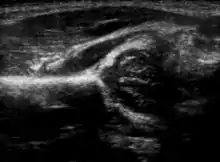

Hip dysplasia can be diagnosed by ultrasound[42] and projectional radiography ("X-ray").[43] Ultrasound imaging is generally preferred at up to 4 months due to limited ossification of the femoral head up until then, and is the most accurate method for imaging of the hip during the first few months after birth. However, in most instances, ultrasound screening should not be performed before 3 to 4 weeks of age because of the normal physiologic laxity.[44][notes 1] When universal with targeted ultrasound screening was compared, the former results in an insignificant reduction in the late diagnosis of hip dysplasia, which is why universal ultrasonographic screening of newborn infants is not recommended by the American Academy of Pediatrics.[11]